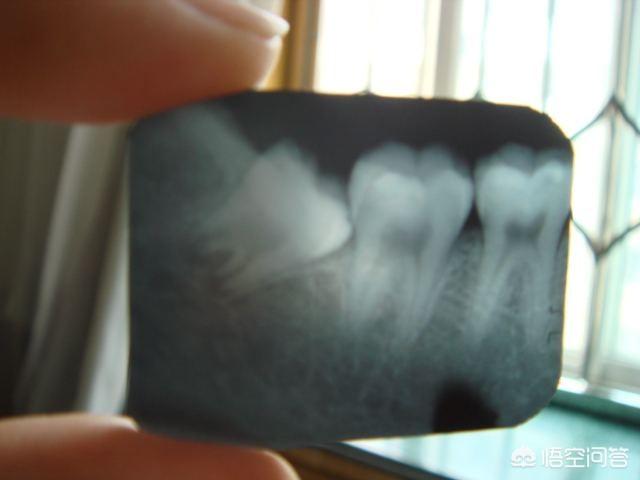

之所以要拔,不是仅仅因为它由于人类进化,食物结构改变后没用了才拔,而最重要的是它还不老实,由于生长空间被其他牙齿挤压而变小了,它大牙特性没有改变,就容易对附近旁边的牙齿进行挤压,而且由于空间小大部分的人长的智齿都是东倒西歪的,如果拍过牙片的人都知道,往往智齿跟旁边牙齿容易形成一个类似三角一样的缝隙,这往往就成了藏污纳垢的地方不易被清洗干净,容易导致发炎(如图)!